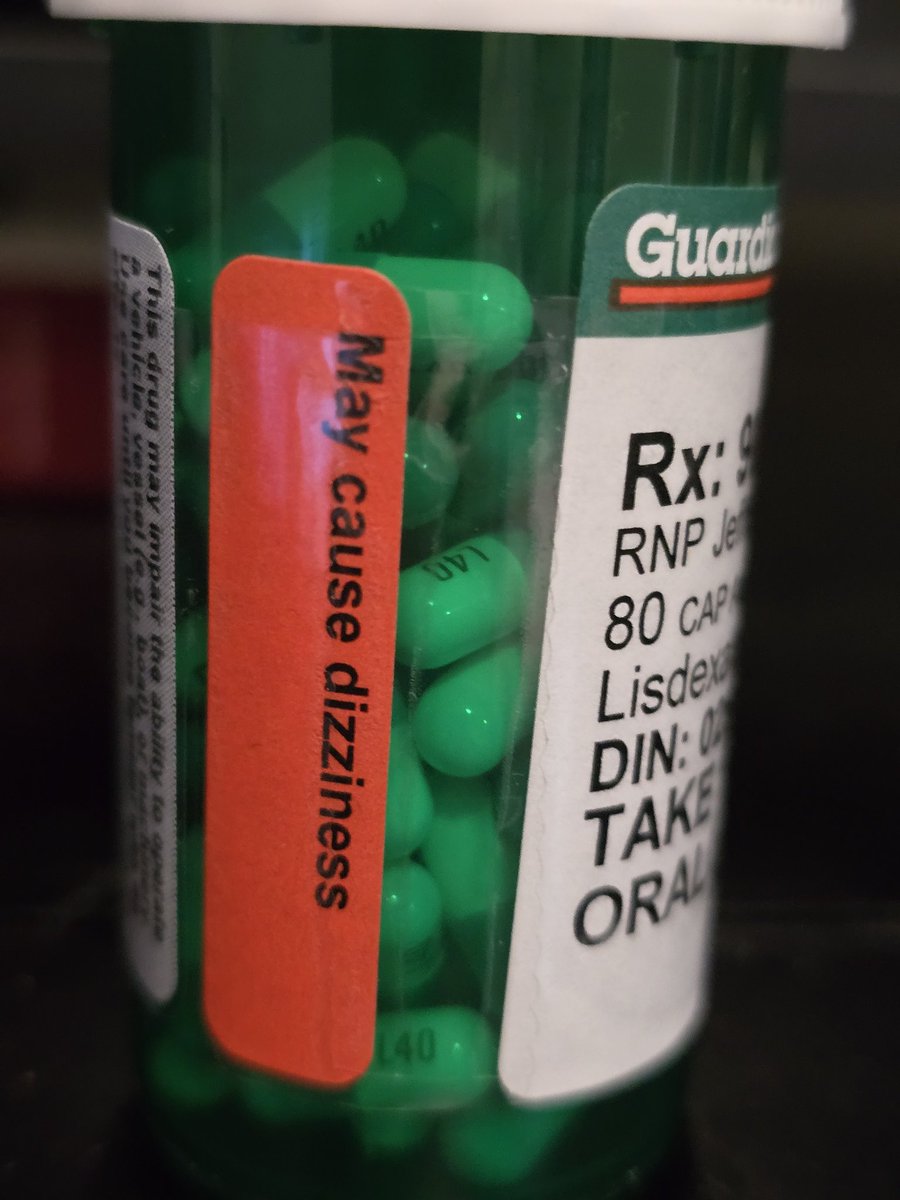

首先,从定义上讲,“反解离(anti-dissociative)”并不是一个标准的医学术语或者广泛认同的药理学分类。在正规资料,比如医学文献、维基百科、精神药理学教科书中,目前并没有“反解离药物”这个正式概念。

看上去像是为了描述某类特定效应而创造的术语(可能是nmda受体活性增强),用来对抗因NMDA受体拮抗剂(比如氯胺酮、DXM、PCP等)引发的解离体验(dissociation)。

那么更常见的是将其归入认知增强剂(cognitive enhancers),特别是改善认知连接性(connectivity)和现实感知(reality testing)的类型。

但其实在药理学上,单纯用“受体激动剂”来逆转“受体拮抗剂”的效应,有时会导致过度激活。

对于NMDA受体而言,过强的NMDA活化本身就与兴奋性毒性(excitotoxicity)和精神病样症状(psychotomimetic effects)有关,比如谷氨酸风暴可以引发严重的焦虑、妄想、乃至癫痫。

也就是说,简单地“激动-解除拮抗”在中枢神经系统是很危险的做法,尤其是对于易感个体(如有精神分裂素质的人)。

科学的处理方式一般是通过更细致的调节,比如微调NMDA/AMPA平衡、调节其他辅助途径(如GABA、5-HT、mGluR受体),而不是简单粗暴地用“NMDA增强剂”去顶回去。

而临床处理药物中毒中,其实医生更常用的做法是保守、支持性的治疗,比如补液,促进代谢,必要时镇静,以及监测生命体征防治并发症。

药物拮抗与受体激动之间,往往牵扯到的是复杂的适应性变化(receptor upregulation/downregulation),

不是简单的“给多一点刺激就能抵消”的关系